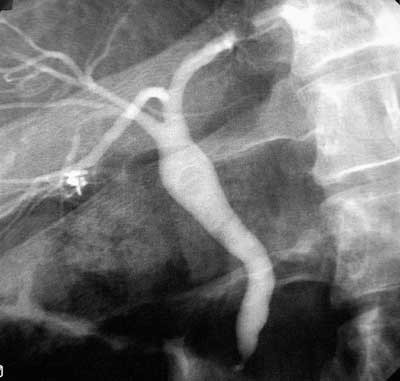

Under det laparoskopiske inngrepet ble det funnet en del adheranser i underkant av leveren, og disse ble delt. Operatøren bemerket at det var påfallende mye luft i tynntarmen. Noen vanlig galleblære kunne ikke påvises, men en del bindevev var lokalisert på galleblærens vanlige plass (fig 1). En strengformet struktur gikk herfra mot ductus choledochus. Den lot seg ikke kanylere med kolangiografikateter. Ingen ektopisk galleblære kunne påvises i leverhilus. Det nevnte bindevevet ble fjernet og inngrepet avsluttet. Operasjonspreparatet målte 3,5 ¥ 0,8 cm, og den mikroskopiske undersøkelsen viste: «Sparsom mengde bindevev og kjertler som kan representere vev fra galleblære, det hele mest forenlig med galleblæreagenesi» (Patologisk-anatomisk avdeling, Universitetssykehuset Nord-Norge). Pasienten fikk noen måneder senere utført endoskopisk retrograd kolangiografi (fig 2). Fem måneder etter operasjonen var ALAT 78 U/l og GT 95 U/l, og bilirubin- og ALP-verdiene var normale. Han ønsket på det tidspunktet ikke noe videre utredning.